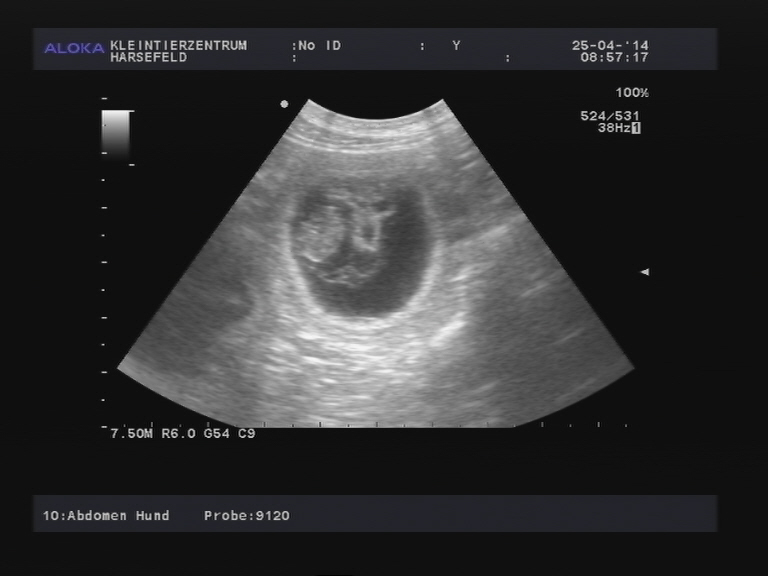

Hier zeigt uns Rosalie nun ihren schönen rosigen Welpenbauch und jeder darf raten,

wieviele Welpen es werden könnten! Die Aufnahme stammt vom 53. Trächtigkeitstag...